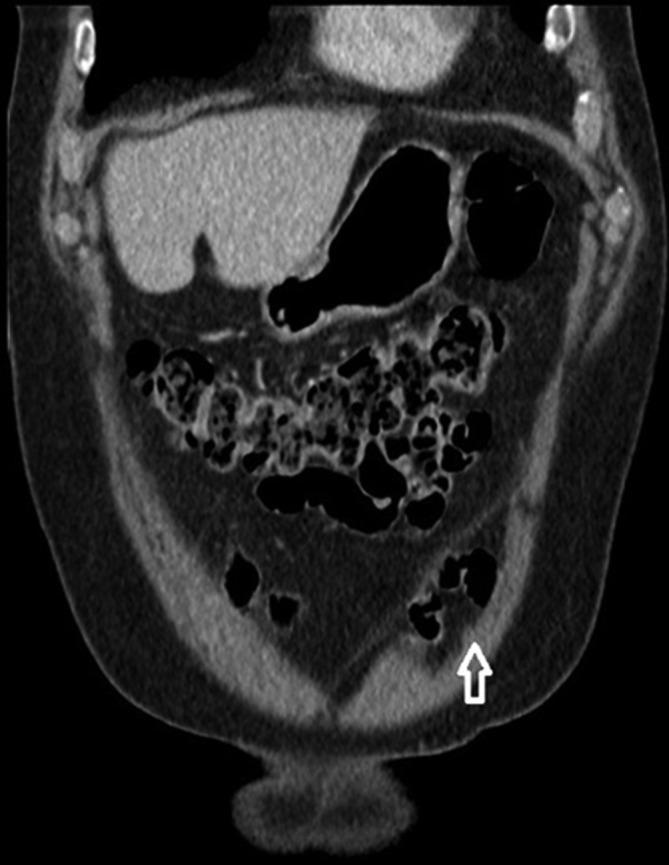

偶然发现的非复杂性腹直肌后鞘疝。

Incidental non-complicated posterior rectus sheath hernia.

Posterior rectus sheath hernia is a truly rare finding, with only 11 documented cases since the first report in 1937. A posterior rectus sheath hernia is herniation of bowel and/or omentum through the posterior portion of the rectus sheath, but not through any other structure. This can only occur medial to the spigelian fascia, differentiating it from a spigelian hernia. Previous missed cases have led to complications such as bowel incarceration, obstruction or even strangulation and have required surgical intervention. In this case report, we describe an incidental finding of a non-complicated posterior rectus sheath hernia in an 83-year-old male. Annotated cross-sectional imaging provides anatomical context that is not widely available in the existing literature. Due to its rarity and potential complications, it is also important to report this case in order to enhance the evidence base for posterior rectus sheath hernia and to familiarize this uncommon condition to radiologists, clinicians and surgeons.

摘要

腹直肌后鞘疝是一种极为罕见的病症,自1937年首次报告以来,仅有11例文献记载。腹直肌后鞘疝是指肠管和/或网膜通过腹直肌后鞘的后部突出,但不通过任何其他结构。这种情况仅发生在半月线筋膜内侧,从而与半月线疝相区别。既往漏诊的病例已导致诸如肠管嵌顿、梗阻甚至绞窄等并发症,且需要手术干预。在本病例报告中,我们描述了一名83岁男性偶然发现的非复杂性腹直肌后鞘疝。带注释的横断面成像提供了现有文献中未广泛提供的解剖学背景。鉴于其罕见性和潜在并发症,报告此病例对于加强腹直肌后鞘疝的证据基础以及让放射科医生、临床医生和外科医生熟悉这种罕见病症也很重要。